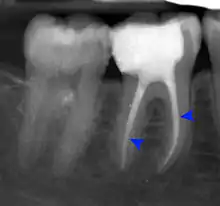

- Radiographs utilized to find dental caries and bone loss laterally or at the apex.

Gutta-percha point indicating abscess origin